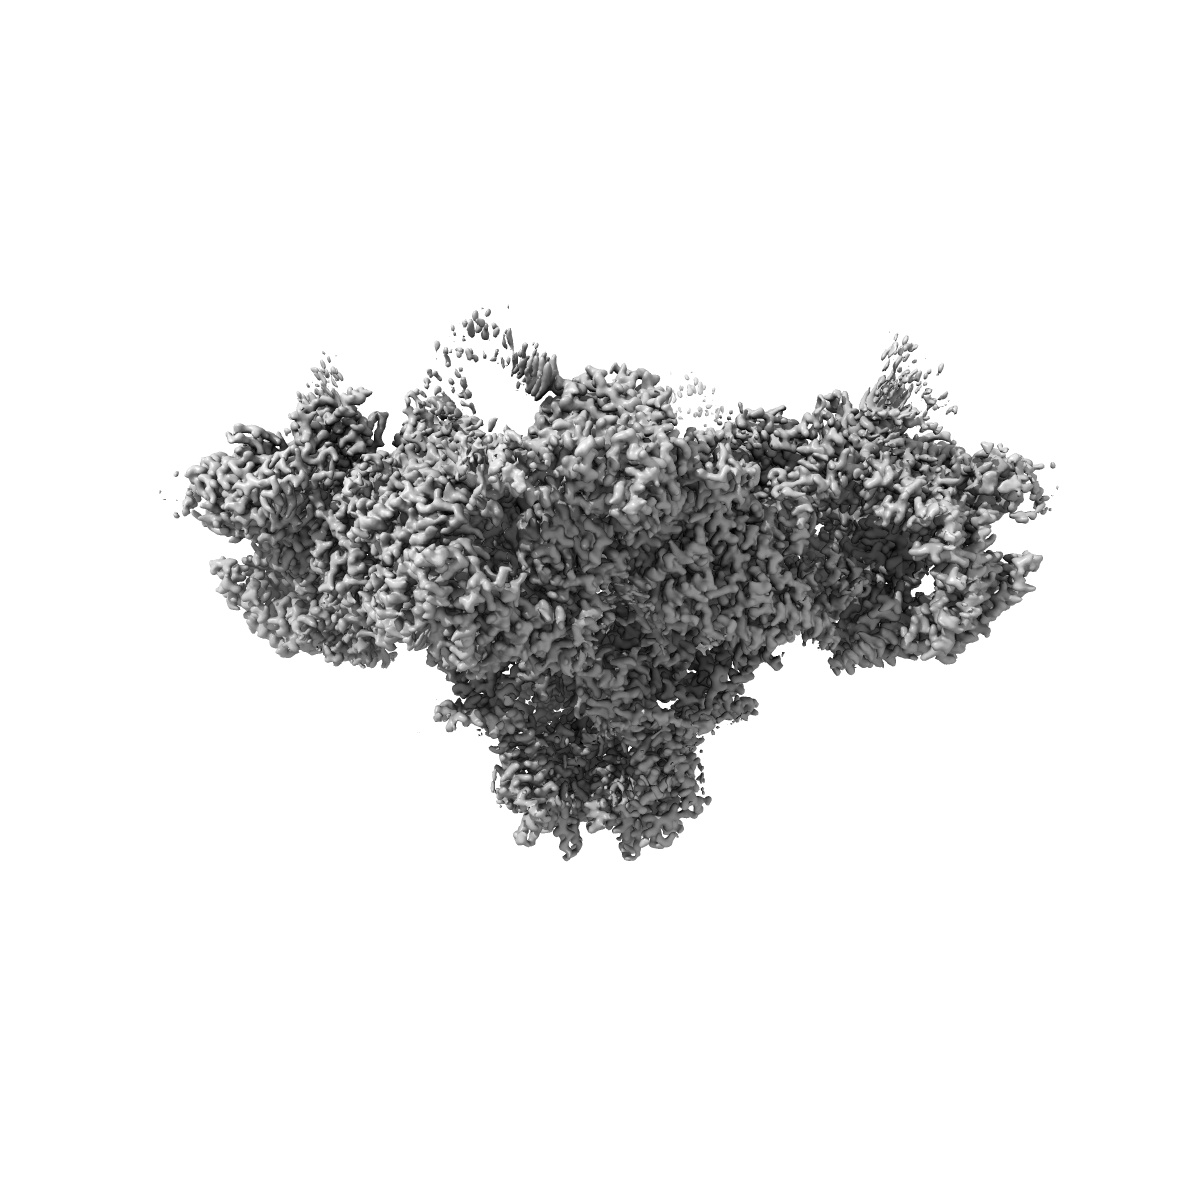

EMD-26205

A drug and ATP binding site in type 1 ryanodine receptor

Single-particle2.45 Å

Sample: Ryanodine receptor 1 complex with calmodulin and calstabin-1